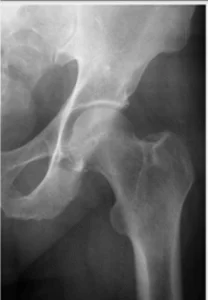

O que é a artrose no quadril?

A artrose é uma doença de origem multifatorial que leva à degeneração da cartilagem articular, afetando todos os componentes da articulação. É um processo lento, progressivo e incapacitante, com alta prevalência na população adulta.

A artrose do quadril é uma das causas mais frequentes de artrose dos membros inferiores, resultando em um impacto negativo na qualidade de vida das pessoas, aumentando o risco de mortalidade e problemas cardiovasculares.